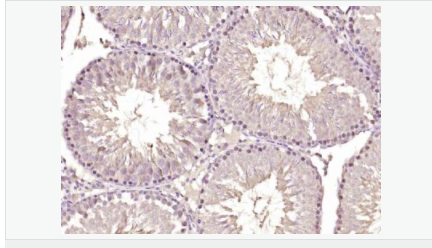

| 產(chǎn)品應(yīng)用 | ELISA=1:5000-10000 IHC-P=1:100-500 IHC-F=1:100-500 IF=1:50-200 (石蠟切片需做抗原修復) not yet tested in other applications. optimal dilutions/concentrations should be determined by the end user. |